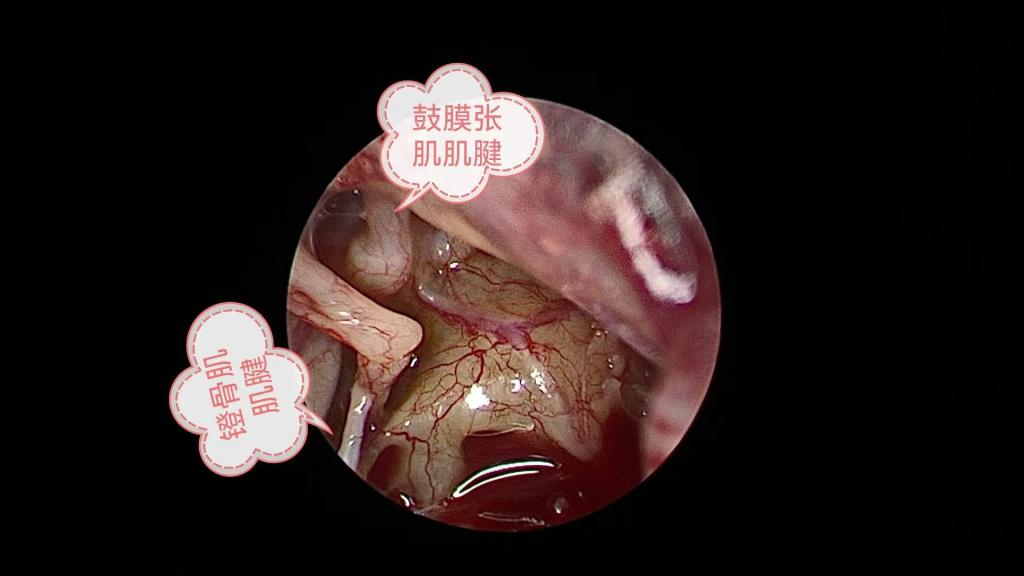

“手术?会不会很危险?要在耳朵上开大口子吗?”面对李女士的担忧,冷辉教授团队给出了定心丸:“这是一种超微创手术,仅在耳道内放入精细的耳内镜,借助屏幕放大的视野,精准切断鼓膜张肌肌腱和镫骨肌肌腱,从根源上阻断眩晕,同时对前庭症状和听力症状产生积极影响。而且手术时间短、出血量少、体表没有任何切口,术后恢复快。”

术中暴露手术视野

切断镫骨肌肌腱和鼓膜张肌肌腱